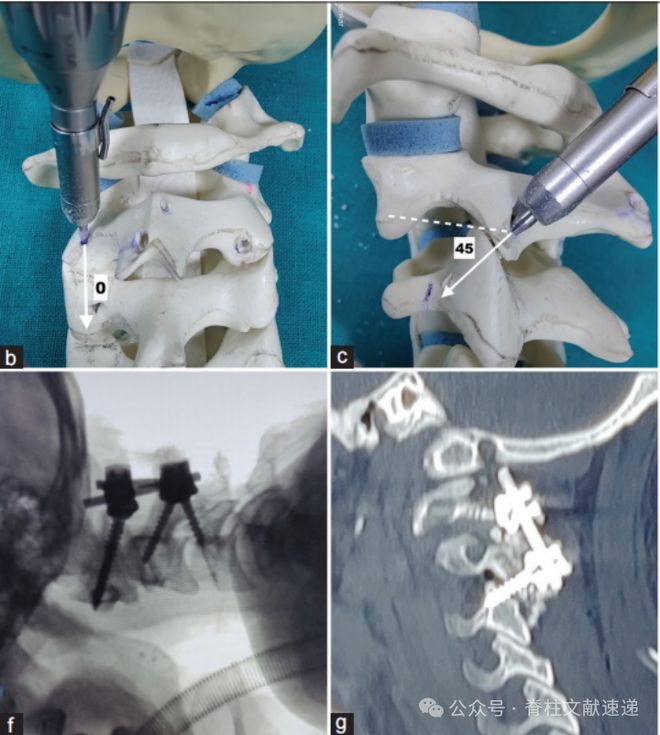

进钉点明显上移的C2椎弓根螺钉,适用于上图所示的情况。可以得到坚强的固定。

如下图所示。该置钉技术距离C1螺钉非常近。可能会存在钉尾打架的情况,安装不上连接棒。此螺钉技术更适合枕颈固定。

上图所示为C2-3经关节螺钉。笔者认为与其这样,不如颈2峡部螺钉+颈3侧块螺钉,或者C2峡部螺钉+C3椎弓根螺钉,反正都是牺牲C2-3活动度。

笔者喜欢改良C2椎弓根螺钉置钉,之前提到过,感兴趣可以在公众号作者精选里查看。